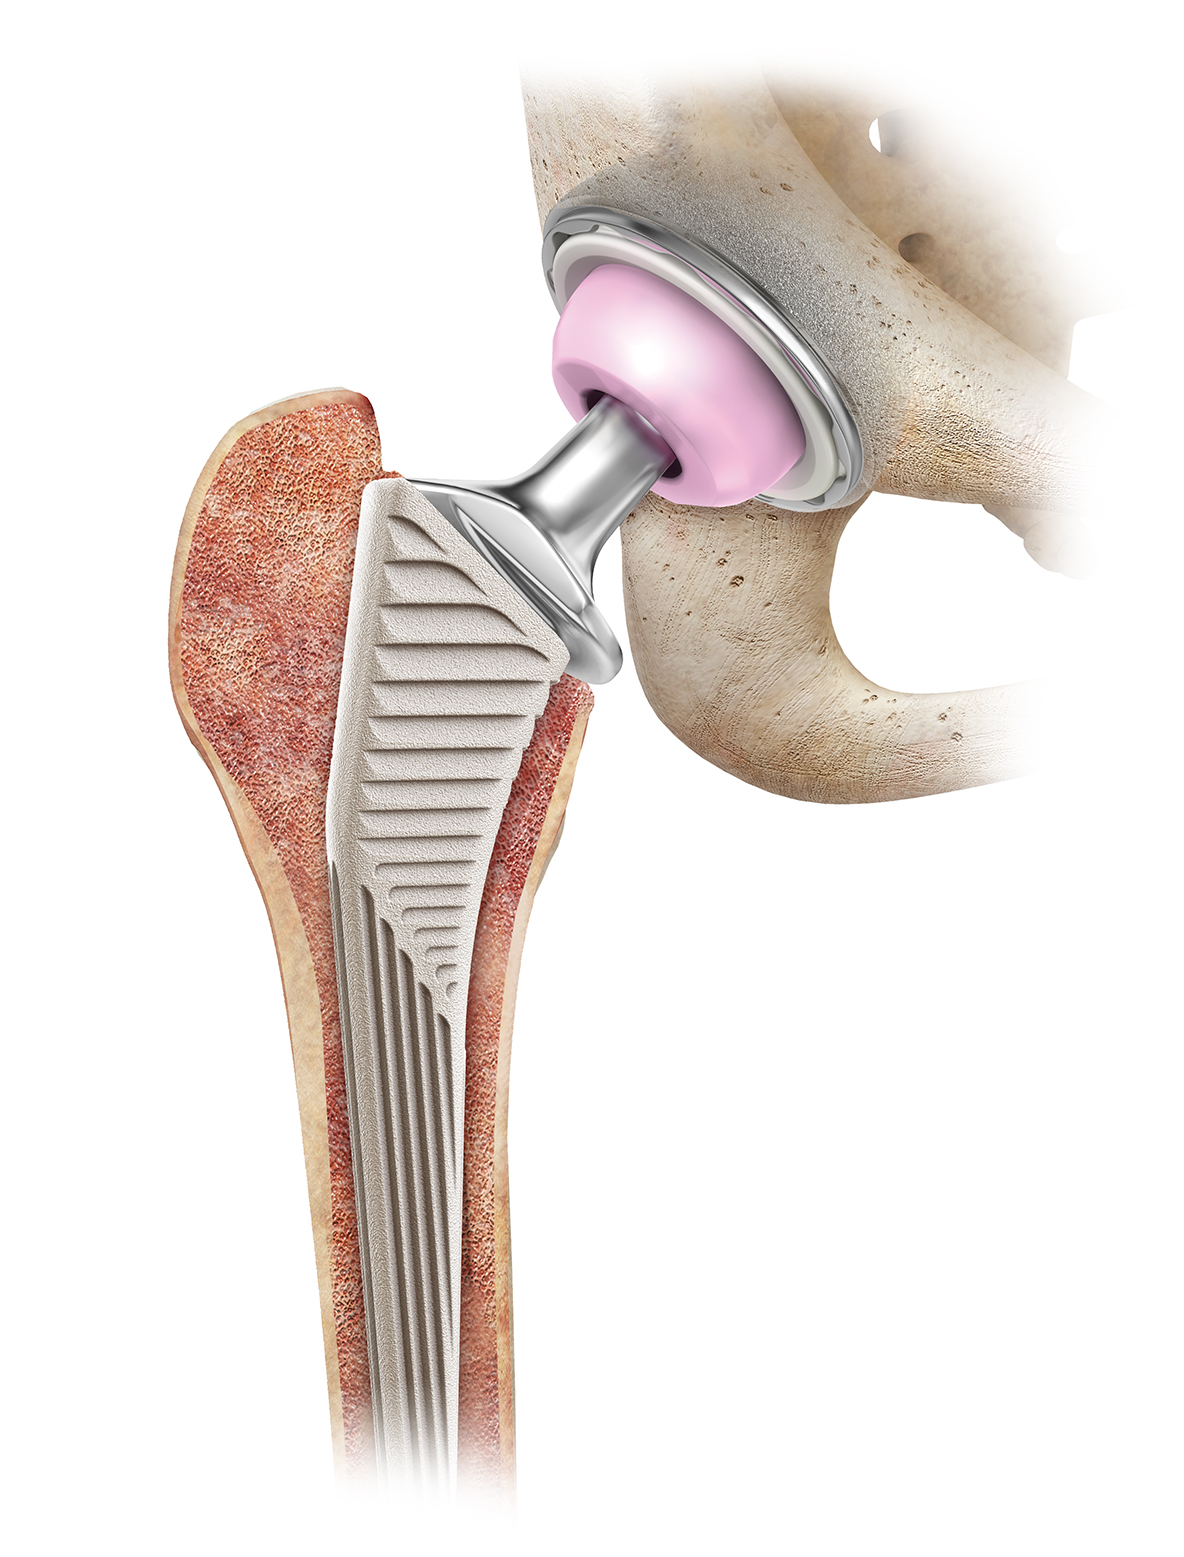

Эндопротезирование тазобедренного сустава: фото и схемы